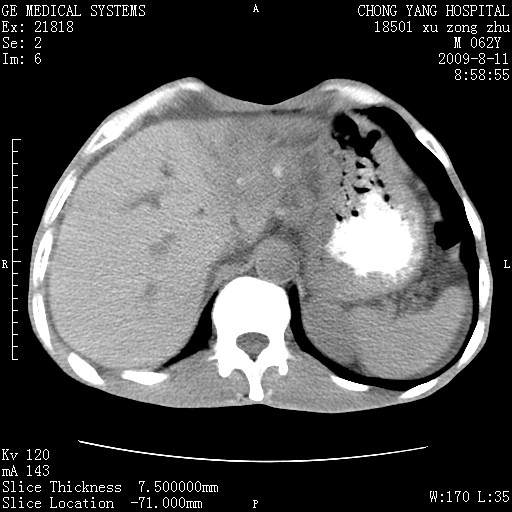

以下是引用杀毒软件在2009-8-11 16:35:00的发言:[br]肝内胆管扩张局限于左叶,胆管内有结石伴肝外胆管结石,胆管壁增厚呈弥漫性并发腹腔积液,胰腺边界模糊。[br][br]考虑---胆总管及肝内胆管结石继发胆管炎及胰腺炎,左肾下极囊肿,腹水。

以下是引用zjzjr在2009-8-11 17:35:00的发言:[br]肝内胆管扩张局限于左叶,胆管内有结石伴肝外胆管结石,胆管壁增厚呈弥漫性并发腹腔积液。[br][br]考虑---胆总管及肝内胆管结石继发胆管炎,左肾下极囊肿,腹水。